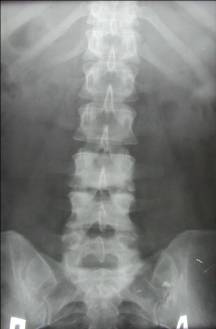

На рентгенограмах до цього часу визначається зменшення висоти або повна відсутність міжхребцевого диска, руйнування прилеглого до цього диску ділянки тіла одного або частіше двох суміжних хребців. Уражаються практично завжди, як і при туберкульозі, тіла хребців. При аналізі структури тел уражених хребців можна відзначити виражений остеосклероз, що дозволяє запідозрити нетуберкульозних природу захворювання (рис.8).

Мал. 8. Хронічний кокковую спондиліт. Контактна деструкція в тілах 2 і 3 поперекових хребців, в суміжних ділянках тіл уражених хребців - дифузний остеосклероз. Висота диска різко зменшена, але проміжок між тілами збережений завдяки потужним підзв'язкового окостеніння по бічних і передньої поверхонь сегмента.

У поперековому відділі абсцес поширюється в поперековій м'язі, зображення зовнішнього контуру якої на рентгенограмі в прямій проекції стає опуклим і асиметричним при порівнянні із симетричною м'язом (рис. 10).

Мал. 10. Спондиліт з частковим руйнуванням міжхребцевого диска L3-4 і контактної деструкцією в суміжних відділах тіл хребців. Розширено межі поперекових м'язів за рахунок псоа-абсцесів (стрілки).

Однак отримати зображення поперекових м'язів далеко не завжди вдається через вмісту кишечника. У таких випадках можна вдатися до зонографіі або лінійної томографії, а де є можливість - до комп'ютерної рентгенівської або магніторезонансної. Абсцеси при хронічному кокковую запаленні рентгенологічно нічим не відрізняються від туберкульозних [10].